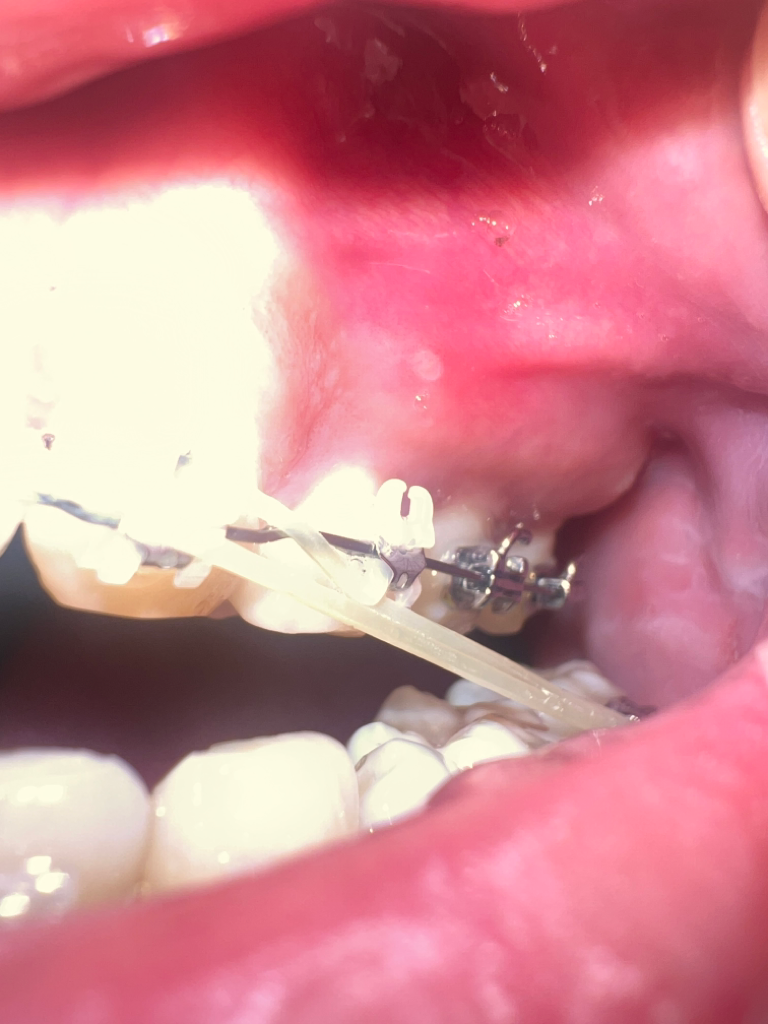

손톱으로 잘못건드려 잇몸 부었어요 구내염인가요??

오늘아침에 잘못해서 손톱으로 긁혔는데 여기가 다른잇몸보다 좀 부어올라있구용.. 흰색으로 뭐가 나있네요 ㅠㅠ 어제 까진 없었는데 단순 염증인가요??

흰색융기는 구내염으로 보입니다 그리고 잇몸도 원래 그렇지 않았는데 부었다면 염증반응이 일어난 것으로 보입니다

또는 해당 부위 잇몸이 아니라 원래 돌출된 뼈 모양일 수도 있습니다

만약 잇몸쪽 부종이 맞다면 원인은 손톱으로 긁어서 그런 것인지 아니면 교정치료 때문인지 파악해봐야 합니다. 교정치료 중에도 잇몸퇴축, 잇몸부종 등의 부작용이 있을 수 있습니다.